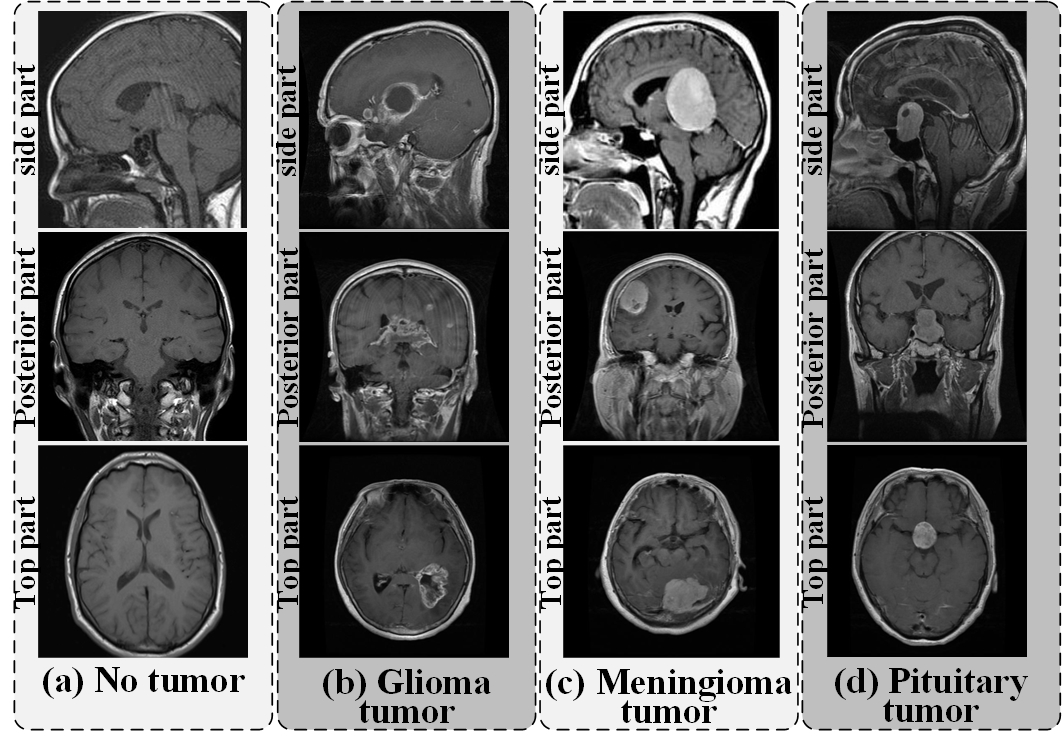

Next, 10,183 brain MRI samples were obtained by collecting online images and merging existing public databases (https://www.kaggle.com/). The samples were of four types: non-tumors (2,396), gliomas (2,547), meningiomas (2,582), and pituitary tumors (2,658), with a relatively balanced range across categories. The size of the dataset used in this experiment is considered above average for this field of study. The training and testing sets were divided in a 9:1 ratio. fig. 5 shows four categories in the brain tumor MRI dataset, including three tumor categories and no tumor: (a) No tumor, (b) Glioma tumor, (c) Meningioma tumor, and (d) Pituitary tumor.

Refer to caption

Figure 5: Four categories of brain MRI samples: (a) No tumor; (b) Glioma tumor; (c) Meningioma tumor; (d) Pituitary tumor. Each category covers three views of brain structures, including the top part, posterior part, and side part samples. All brain tumor MRI images come from public open databases without any privacy information.